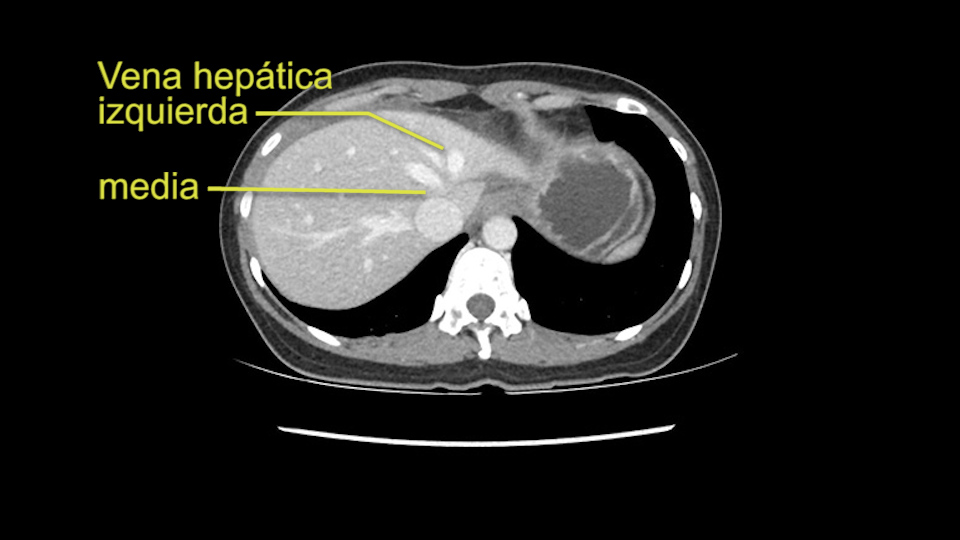

Anatomically, to plan for a left lateral segmentectomy, it’s relatively easy as far as liver surgery goes. I know that I'm going to be looking for the left hepatic vein which will be divided at some point either towards the end at the back near the vena cava or through the middle of the left lateral segment.

The transection line will be a little more obvious. There’s a little patch of focal fat here in Segment 4b but we’ll describe the transection line probably through the mid portion of Segments 4a and b up to the top. Up at the top, the left hepatic vein can be taken. There’s a Segment 3 vein or the so-called falciform vein it’ll be rudimentary so I think we’ll be able to get around the left hepatic vein and leave the middle [hepatic] vein intact because it’s free of tumor.

The other option of course is to do an anatomical left hepatectomy. In that case, I will start mobilizing of course the left lobe and try to find the ligamentum venosum, take it down and go around the left hepatic vein. I think, importantly in these cases and in this case, as you can see in the venous phase, that’s clearly a moment to stop. Because the left hepatic vein is pretty close to the middle hepatic vein as sometimes it is so you may need to dissect a little bit the parenchyma on top of the left hepatic vein to be able to go around the left hepatic vein safely.

En cuanto a la hepatectomia izquierda aquí creo que la clave va a ser disecar bien el ligamento venoso y poder ir pasar una cinta alrededor de la vena hepática izquierda, en este caso parece que al vena hepática izquierda está muy junta, como en muchos casos a la vena hepática media, a ser importante disecar bien la vena supra hepática izquierda para poder pasar alrededor de ella sin dañar la cava o la vena hepática media. Una vez que hayamos hecho esto pasaremos a mirar la porta, y yo siempre tiendo a disecar las estructuras lo mas próximas al hígado posible, disecaremos la arteria hepática media rama del segmento 2-3 y la rama del segmento 4 si estamos haciendo una hepatectomia izquierda, y insisto parce que este tumor además tiene otras muchas ramas que van directas al tumor que habrá que ligar, eso nos dará acceso a la vena porta izquierda que probablemente resecare con una grapadora lineal, y finalmente transectarmos, haremos la transeccion hepática.